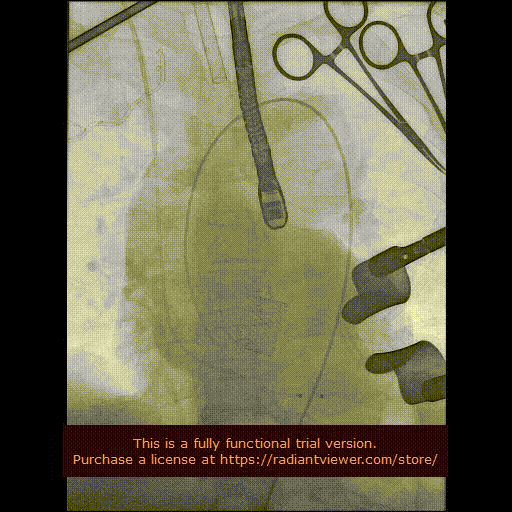

造影显示主动脉窦部

从心尖置入输送系统

定位件入窦

瓣膜降至瓣环平面

释放瓣膜

造影确认瓣膜位置

撤出输送系统

造影确认植入效果